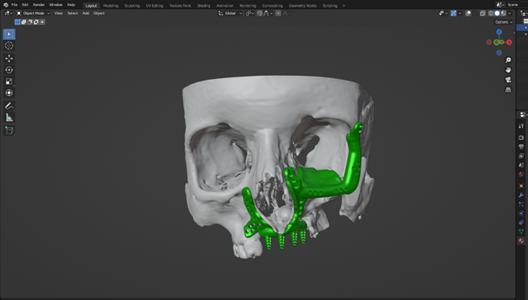

The patient suffered significant trauma to the right side of her face, including partial loss of her right eye, a laceration to the upper jaw, and damage to the orbital floor. Through detailed CT scan analysis and the use of Blender—a professional-grade 3D design software—the medical engineering team reconstructed the affected facial structure and designed a highly accurate, patient-specific implant to restore both functionality and appearance.

This personalized implant serves as a precise anatomical replacement for the missing bone structure and represents a major step toward 3D printing it in a biocompatible material such as titanium. The goal is not only to restore facial aesthetics but also to support improved medical outcomes and quality of life.

As part of UOWA’s broader vision, this work reflects the hub’s mission to bridge advanced technology with compassionate care, transforming the future of trauma recovery and reconstructive surgery in Iraq and beyond.